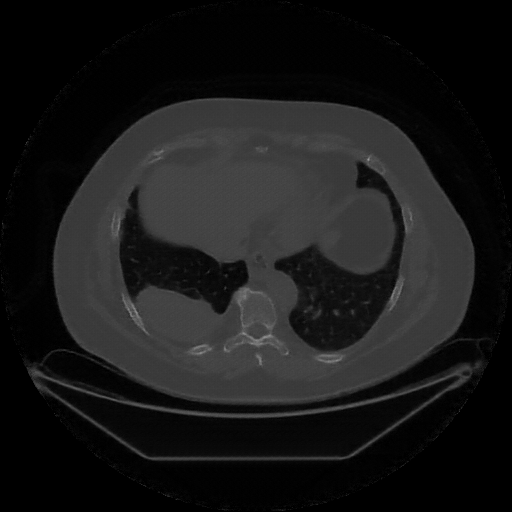

Image Grid

4Γ—3 grid: Rows show different image types (Original NATIVE, Reconstructed NATIVE, Original VENOUS, Generated VENOUS), Columns show windowing techniques (No Window, Lung Window, Mediastinum Window)

Lung window (WL -600, WW 1500 β†’ Low βˆ’1350, High +150)